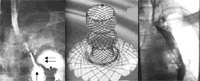

图1 食管胃吻合口-胸腔瘘患者碘水食管造影图

口服碘水造影显示对比剂大量经食管胃吻合口溢入左侧胸腔(单箭头处胃腔,双箭头处胸腔内对比剂),食管与胃几乎完全相互分离。

图2 蘑菇状覆膜内支架实物图

图3 该患者置入支架后碘水造影图

置入一枚22 mm ×(60 mm~80 mm)蘑菇状覆膜内支架封堵瘘口,内支架完全释放后,口服碘水造影显示对比剂通过残留食管经内支架顺利进入胃腔,无对比剂外溢。, 百拇医药